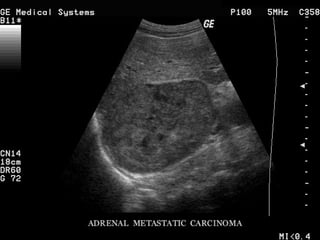

TUMORES METASTÁTICOS 6 – 38 % Mama Pulmão Rim Linfomas Melanomas História prévia tumores Lucon AM, Latronico AC. Doenças benignas e malignas das supra-renais. In: Barata HS, Carvalhal GF. Urologia - Princípios e Prática. Pp. 581-7, ed. ArtMed. 1999

TUMORES METASTÁTICOS 6– 38 % Mama Pulmão Rim Linfomas Melanomas História prévia tumores Lucon AM, Latronico AC. Doenças benignas e malignas das supra-renais. In: Barata HS, Carvalhal GF. Urologia - Princípios e Prática. Pp. 581-7, ed. ArtMed. 1999